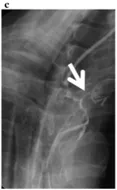

食管癌患者在食管部分切除后進行食管胃吻合,一旦發(fā)生吻合口漏,致死率很高,因此,它是食管賁門手術后最嚴重的并發(fā)癥。發(fā)生吻合口漏的主要原因為吻合口血運不良,吻合口張力過大。此外,縫合時吻合口對合不佳,縫合針距過小或過大,過疏或過密,結扎過緊或過松等均可能發(fā)生吻合口漏。 發(fā)生吻合口漏的患者主要臨床表現有術后不能解釋的發(fā)熱、脈快、氣短等全身感染中毒癥狀,嚴重時短期即可造成呼吸、循環(huán)衰竭。頸部吻合者體溫僅中度升高,切口局部腫脹、疼痛和壓痛。胸內吻合口漏中毒癥狀最嚴重,胸腔穿刺抽得含臭味的渾濁液體。 診斷時需要結合臨床表現和上消化道鋇餐造影檢查,若發(fā)現發(fā)現造影劑外溢,口服亞甲藍后胸腔穿刺抽出藍染胸液,即可明確診斷。 (食管造影顯示新建食管腔外造影劑滲出) 吻合口漏多發(fā)生在術后1周左右,根據發(fā)生的時間、漏口大小、部位以及患者全身狀況,采取相應的治療方法。保守治療原則為充分引流,控制感染,維持營養(yǎng)和水、電解質平衡,盡快恢復經口進食。手術治療新吻合多不成功,僅在某些病例可考慮施行。一般多先行一段時間保守治療,有條件時再行二期重新吻合,或帶蒂組織瓣修補破損的漏口,或食管頸部外置后結腸間置代食管。